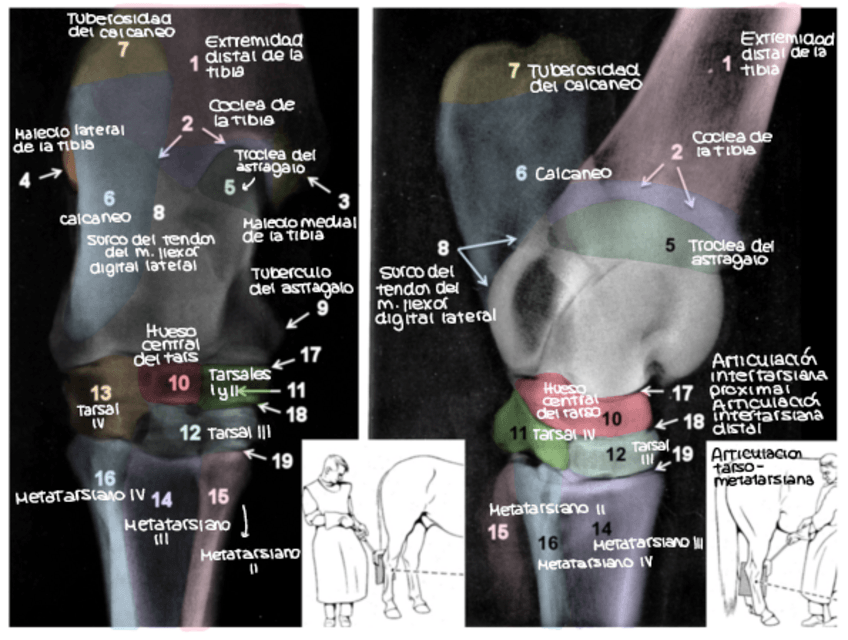

He publicado nuevos apuntes de 1º EMBRIOLOGÍA Y ANATOMÍA I: TEST-4-Radiografias-corregido.pdf

10 páginas